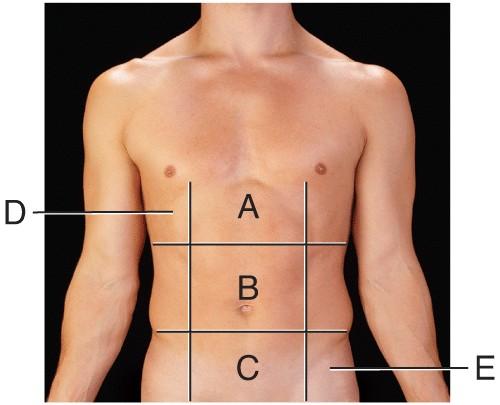

Name the region B.

middle hypochondriac

hypogastric

epigastric

Umbilical

Umbilical

Name the region A.

epigastric

umbilical

right hypochondriac

hypogastric

epigastric

Name the region E.

left hypochondriac

right lumbar

epigastric

left iliac

left iliac

Name the region C.

middle iliac

epigastric

umbilical

hypogastric

hypogastric

Name the region D.

Right Hypochondriac

Left Hypochondriac

epigastric

Right Lumbar

Right Hypochondriac

The liver is found in the region labeled:

A